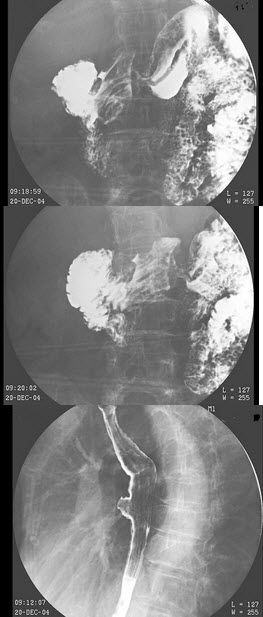

191、单项选择题

男,55岁,左侧舌下肿胀不适2个月余,体检发现左侧舌下肿胀,舌下阜处可见脓苔黏附,触痛,按之可见淡黄色脓液从舌下阜溢出,摄片如图所示,最可能诊断()

A.左侧颌下腺涎石

B.左侧舌下腺涎石

C.左侧腮腺涎石

D.正常影像

E.左侧下颌骨含牙囊肿

点击查看答案